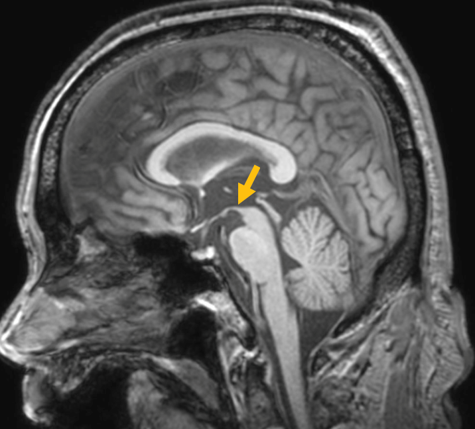

진행 핵상 마비는 대표적인 파킨슨 증후군 중의 하나입니다. 파킨슨병과 다른 점은 질병의 초기부터 중심을 잡기 어려운 체위 불안정이 나타나 자주 넘어진다는 것입니다. 파킨슨병의 경우 질병이 상당히 진행된 뒤에 체위 불안정이 나타납니다. 또한 진행 핵상 마비에서는 목 주위 근육을 비롯한 몸 중심 근육의 경축이 나타나, 목을 뒤로 젖히면서 걷는 모습이 보입니다. 그리고 눈의 운동을 조절하는 기능에 장애가 나타나 아래쪽을 바라보는 데 문제가 생겨 계단을 내려갈 때 어려움을 겪는 경우가 많습니다. 진행 핵상 마비가 의심되는 경우, 뇌 자기공명영상(MRI)에서 중뇌의 위축이 비정상적으로 심하게 나타나는 소견을 확인하거나, 뇌포도당 양전자 단층촬영(PET)에서 전두엽과 중뇌의 대사 기능이 저하된 소견을 확인하여 진단에 참고할 수 있습니다.

[진행핵상마비 환자의 뇌자기공명영상에서 확인되는 중뇌 위축 소견]

[진행핵상마비 환자의 뇌포도당 양전자 단층 촬영에서 확인되는 중뇌의 대사 저하 소견]2. 다계통 위축(Multiple system atrophy)